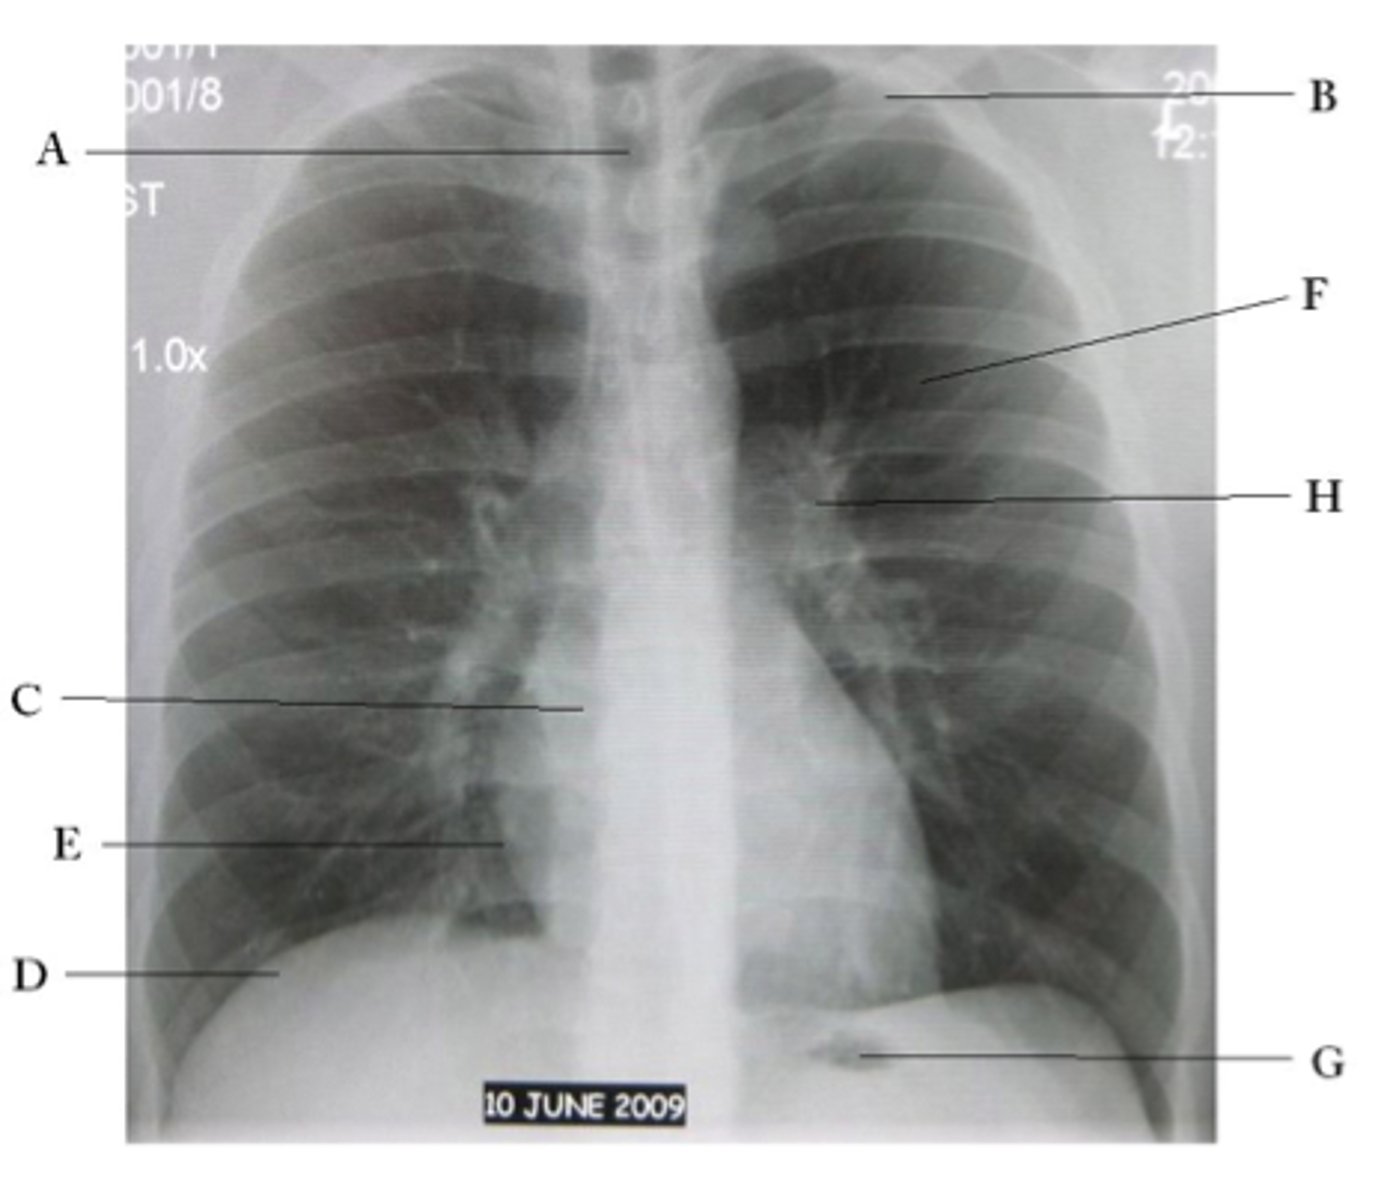

A

trachea

B

Clavicle

C

Right atrium

D

Diaphragm

E

Cardiophrenic angle

F

left upper lobe

G

gastric bubble

H

Left hilum